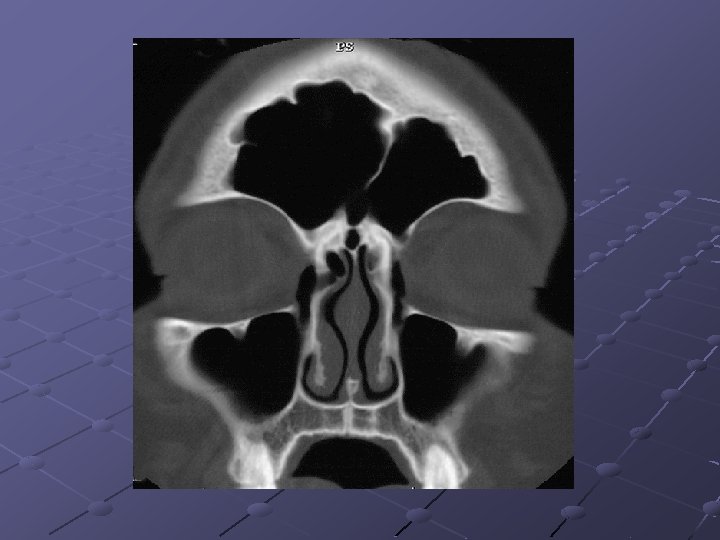

CRS 78 had criteria to CRS 17 endoscopy: positive 37 - CT findings: positive 6 endoscopy : positive 41 - CT findings: negative 35: endoscopy negative & CT negative 20: endoscopy negative & CT positive 55: endoscopy negative Stankiewicz & Chow: Otolaryngol Head Neck Surg 2002

Radiology & clinical exam Correlated with a Sensitivity of 75% And specificity of 84% Endoscopy correlated poorly with sinus disease and not predictive Stankiewicz & Chow: Otolaryngol Head Neck Surg 2002

Endoscopy/ct findings/clinical Easy to diagnose CRS by endoscopy alone when nasal polyps, purulence, or fungus is observed, when absent, establishing the diagnosis may be more difficult 45% of patients with clinical CRS were both endoscopically and radiographically negative. Stankiewicz and Chow. Otolaryngol head neck surg 2002

Endoscopy/ct findings/clinical Negative endoscopy alone is insufficient to rule out sinusitis. 26% of patients who were negative on endoscopy had positive CT – this would suggest that if endoscopy is negative most of the time the ct will be also negative, even with a positive history. Stankiewicz & Chow: Otolaryngol Head Neck Surg 2002